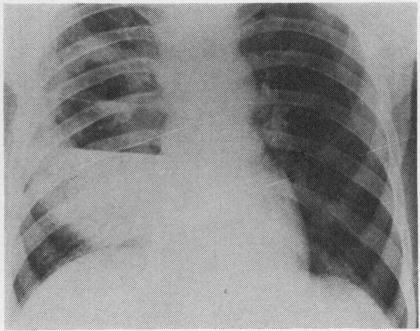

食管念珠菌病导致瘘管形成和肺脓肿。

Oesophageal moniliasis causing fistula formation and lung abscess.

Oesophageal moniliasis is reviewed and the incidence of fistula formation discussed. A case of oesophageal moniliasis without any predisposing factors, with fistula formation and lung abscess, is presented.

对食管念珠菌病进行了综述,并讨论了瘘管形成的发生率。本文报告了一例无任何诱发因素的食管念珠菌病病例,该病例伴有瘘管形成和肺脓肿。